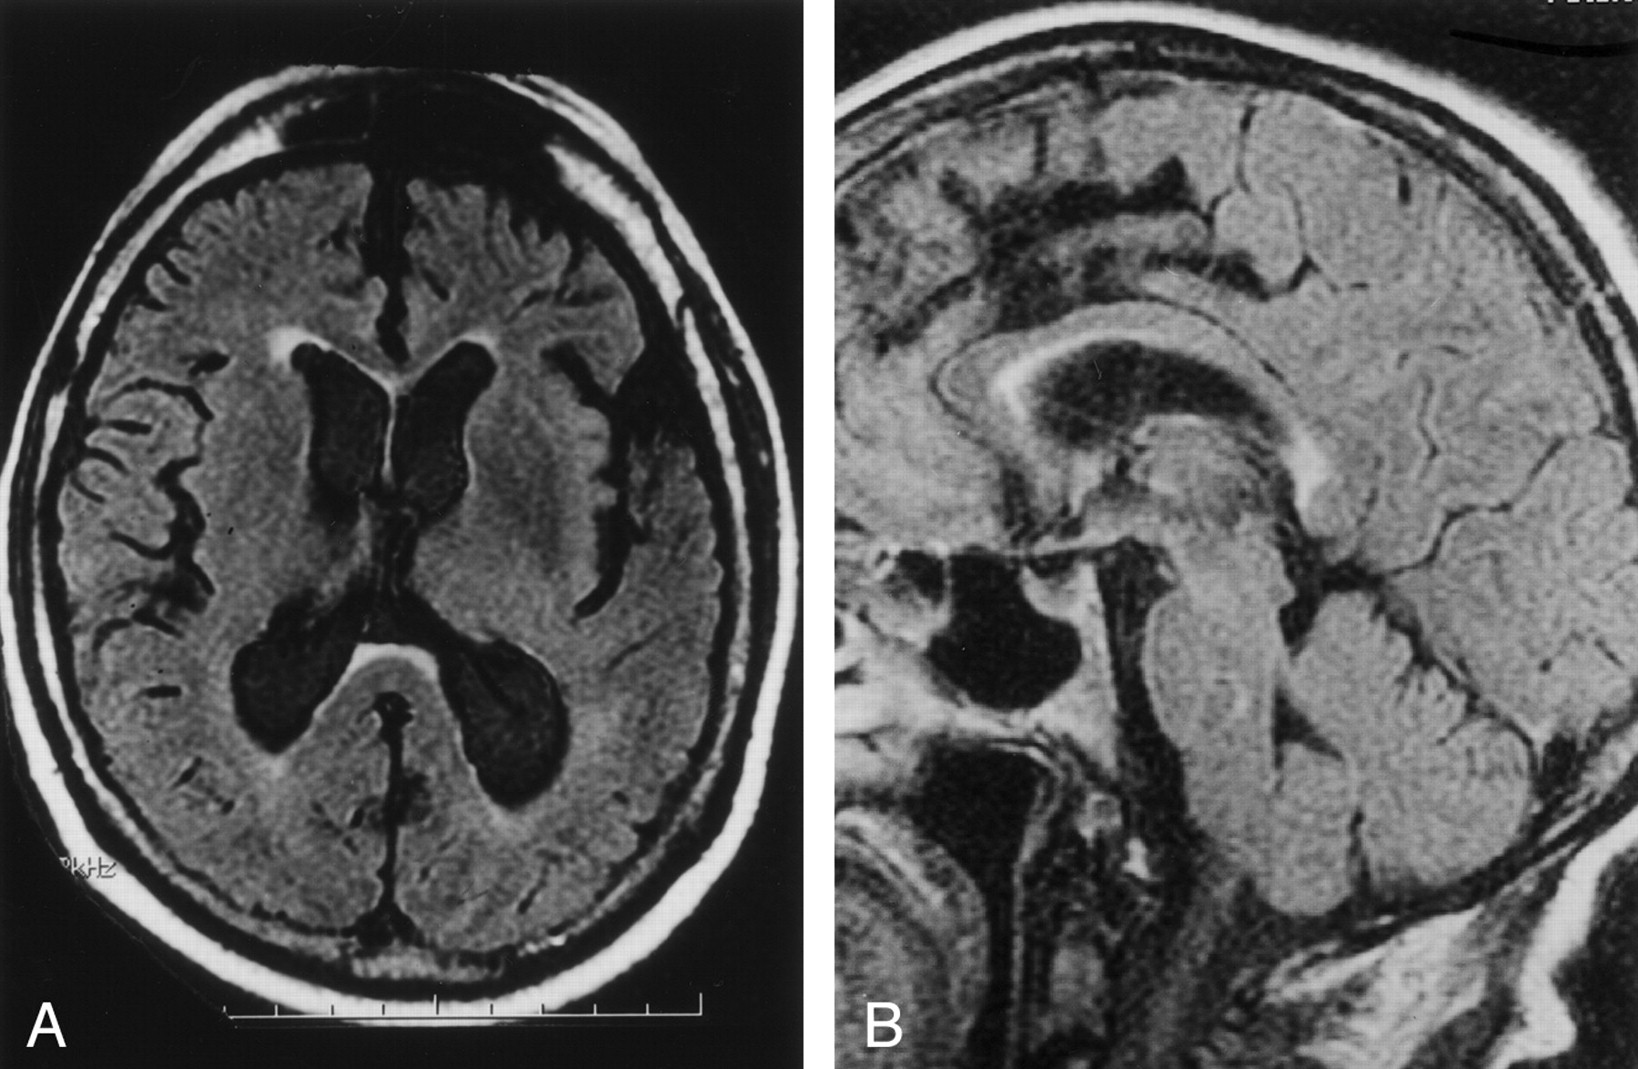

Among the initial 67 patients who were imaged as part of their clinical evaluation for suspected CNS disease, 32 patients demonstrated increased signal intensity in the splenium of the corpus callosum on FLAIR images (Fig 1). Eleven of these patients with abnormal signal intensity underwent prior brain radiation therapy. In the sample of all 67 patients, age, history of radiation therapy, and white matter signal intensity abnormality grade were all significant predictors of splenial lesion grade on simple correlational analyses (all P < .001). Regression analysis confirmed that history of radiation therapy and white matter lesion grade each accounted for a significant proportion of variance in splenial lesion grade (P < .001), whereas the effect of age dropped to a nonsignificant level (P > .05) when the effects of the other two variables were entered into the equation. The sample was divided into two subsets for all subsequent analyses: 54 patients with no history of radiation therapy and 13 patients with a history of brain and neck radiation therapy.

Case of a 67-year-old patient imaged to rule out aneurysm.

A, Axial and B, sagittal FLAIR MR images (10,000/156/1) show high signal intensity in the anterior subependymal region of the splenium of the corpus callosum, involving more than half the thickness (grade 2).

The first subset, 54 patients evaluated for suspected CNS disease, was composed of 34 female and 20 male patients with a mean age of 50.4 ± 23.5 years (range, 3–93 years). Of this subset, 19 (35%) demonstrated increased signal intensity in the splenium of the corpus callosum. This signal intensity abnormality was most typically seen involving the anterior subependymal region of the splenium on axial and sagittal FLAIR images (Fig 1). Within this group, splenial abnormality, white matter abnormality (each coded as present or absent), and age all significantly and positively correlated with each other (all P < .001). Given the dichotomous nature of the variables involved, a distribution-free analysis was used to confirm the positive relation between the presence of splenial lesions and white matter abnormalities (χ24 = 51.8, P < .001). To provide a preliminary evaluation of the relative contribution of age and white matter abnormality to the prediction of splenial lesions, a stepwise regression analysis was conducted, with splenial abnormality as the dependent variable and white matter abnormality and age as independent variables. Results indicated a significant relation between the presence of white matter abnormalities and splenial abnormalities (R2adj = 0.74, P < .001). After accounting for variance in splenial status associated with white matter abnormality, age did not enter into the equation. To further explore the relation between white matter and splenial abnormalities, a count was taken of the number of cases in which splenial lesion grade was greater than, equal to, or less than white matter lesion grade. Although the ratings were made independently, most cases (n = 45 [83%]) showed the same lesion grade for both white matter and splenium. Only nine cases showed a mismatch between splenial and white matter lesion grades, most of which (n = 8) involved a higher grade for white matter than for splenial lesion.